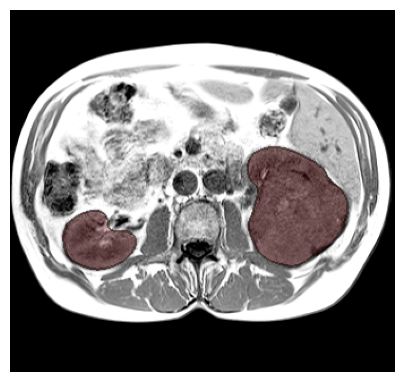

Purpose: To introduce a deep learning model capable of multi-organ segmentation in MRI scans, offering a solution to the current limitations in MRI analysis due to challenges in resolution, standardized intensity values, and variability in sequences. Materials and Methods: he model was trained on 1,200 manually annotated MRI scans from the UK Biobank, 221 in-house MRI scans and 1228 CT scans, leveraging cross-modality transfer learning from CT segmentation models. A human-in-the-loop annotation workflow was employed to efficiently create high-quality segmentations. The model's performance was evaluated on NAKO and the AMOS22 dataset containing 600 and 60 MRI examinations. Dice Similarity Coefficient (DSC) and Hausdorff Distance (HD) was used to assess segmentation accuracy. The model will be open sourced. Results: The model showcased high accuracy in segmenting well-defined organs, achieving Dice Similarity Coefficient (DSC) scores of 0.97 for the right and left lungs, and 0.95 for the heart. It also demonstrated robustness in organs like the liver (DSC: 0.96) and kidneys (DSC: 0.95 left, 0.95 right), which present more variability. However, segmentation of smaller and complex structures such as the portal and splenic veins (DSC: 0.54) and adrenal glands (DSC: 0.65 left, 0.61 right) revealed the need for further model optimization. Conclusion: The proposed model is a robust, tool for accurate segmentation of 40 anatomical structures in MRI and CT images. By leveraging cross-modality learning and interactive annotation, the model achieves strong performance and generalizability across diverse datasets, making it a valuable resource for researchers and clinicians. It is open source and can be downloaded from https://github.com/hhaentze/MRSegmentator.